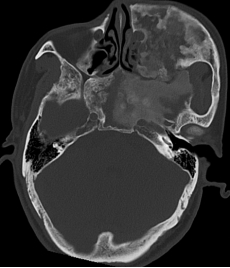

经详细检查,医生确诊吴叔叔患有颅面骨纤维异常增生症,其病变组织大小约5.6×9×5厘米。骨纤维异常增生症是由先天基因突变引发的良性病变,病变区域的正常骨组织会被异常的纤维骨组织替代。由于吴叔叔病程长达数十年,异常增生的骨质已向颅底蔓延,而颅底周边分布着视神经、脑垂体等重要组织器官,手术操作空间狭小,术中稍有不慎便可能造成神经、器官损伤,引发严重并发症,手术难度与风险极高。

为保障手术安全顺利实施,耳鼻咽喉头颈外科副主任、鼻科主任、主任医师李泉带领团队多次开展病例研讨,反复优化手术方案。手术过程中,副主任医师刘勇、主治医师谢盼凭借精湛的手术技巧和丰富的临床经验精准操作、攻坚克难,不仅完整切除颅底异常增生的病变组织,还为患者实施了双侧视神经解压术。整个手术团队紧密协作、各司其职,顺利克服术中诸多难点,成功完成手术。